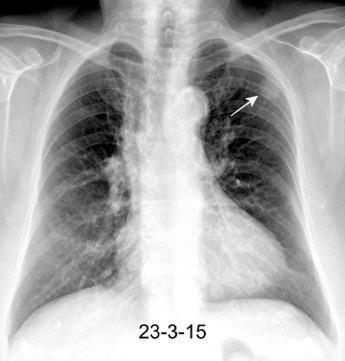

Nódulo en língula.

Cirugía de Ca .de mama hace 23 añosedema de brazo y ganglio en axila. ¡Metástasis!.